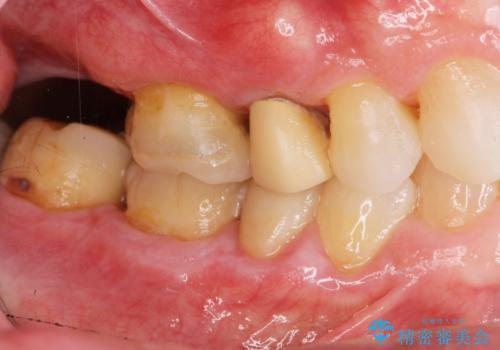

- かぶせてある歯が数日前からぐらぐらするので付け直してほしい、と希望され来院されました。

かぶせ(以下クラウン)を外してみたところ、神経のない支台となる歯が折れてしまい抜歯を余儀なくされる状況でした。